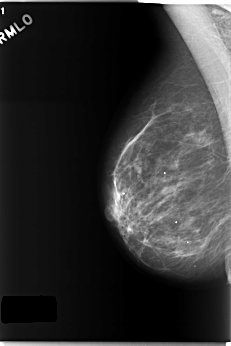

C_0218_1.RIGHT_CC

RIGHT_CC LINES 5952 PIXELS_PER_LINE 3896 BITS_PER_PIXEL 12 RESOLUTION 50 NON_OVERLAY